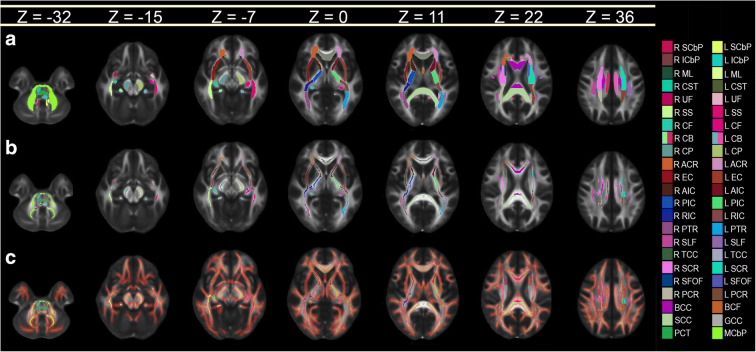

WM voxels were mapped onto WM structures in Montreal Neurological Institute (MNI) MNI152 space using FSL version 6.0.1 and the Johns Hopkins University (JHU) International Consortium of Brain Mapping (ICBM) DTI81 WM labeling scheme. First, the mean FA skeleton mask was co-registered onto the JHU label map, thereby creating a skeletonized version of the latter. Images were then binarized such that voxels corresponding to statistical significance (p < 0.05) were set to 1, whereas remaining voxels were set to 0; these binarized images were then projected onto the skeletonized label map. The total number of significant voxels in the volume associated with each label was divided by the total number of voxels pertaining to that label so as to calculate the percentage volume of voxels associated with statistical significance and located in each structure. Results were represented graphically for visual interpretation. For cortical thickness calculations, after binarizing each subject’s cortical surface overlay based on statistical significance (1 = significant; 0 = not significant), the resulting binary map was registered onto the average cortical surface in the Desikan–Killiany atlas. Then, a similar procedure was used to calculate the percentage of cortical surface area within each cortical region which contained vertices associated with statistical significance. Figure 1 illustrates a conceptual representation of this process.

Fig. 1.

Conceptual representation of the process for calculating the percentage of voxels associated with statistically significant findings within each neuroanatomic structure. (a) WM label map of the JHU atlas. (b) Mean WM skeleton mask of all subjects in the study. (c) Voxels where mTBI subjects exhibit mean FA values which are significantly lower (p < 0.05) than in HCs. The voxel map is overlaid on the skeletonized label map of the atlas, which is thickened for easier visualization. All images are overlaid on the 1 mm × 1 mm × 1 mm FMRIB58 FA template, which is an average of FA maps across 58 healthy subjects. Colors encode various WM structures (see Tables 2, 3, and 4 for abbreviations)